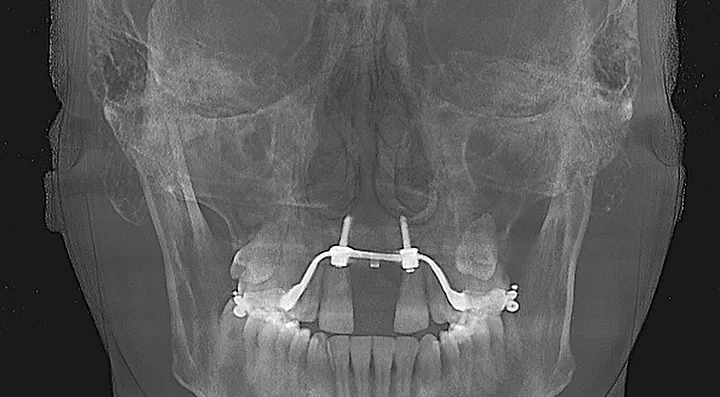

look how the maxilla was ripped apart on this one holy chit